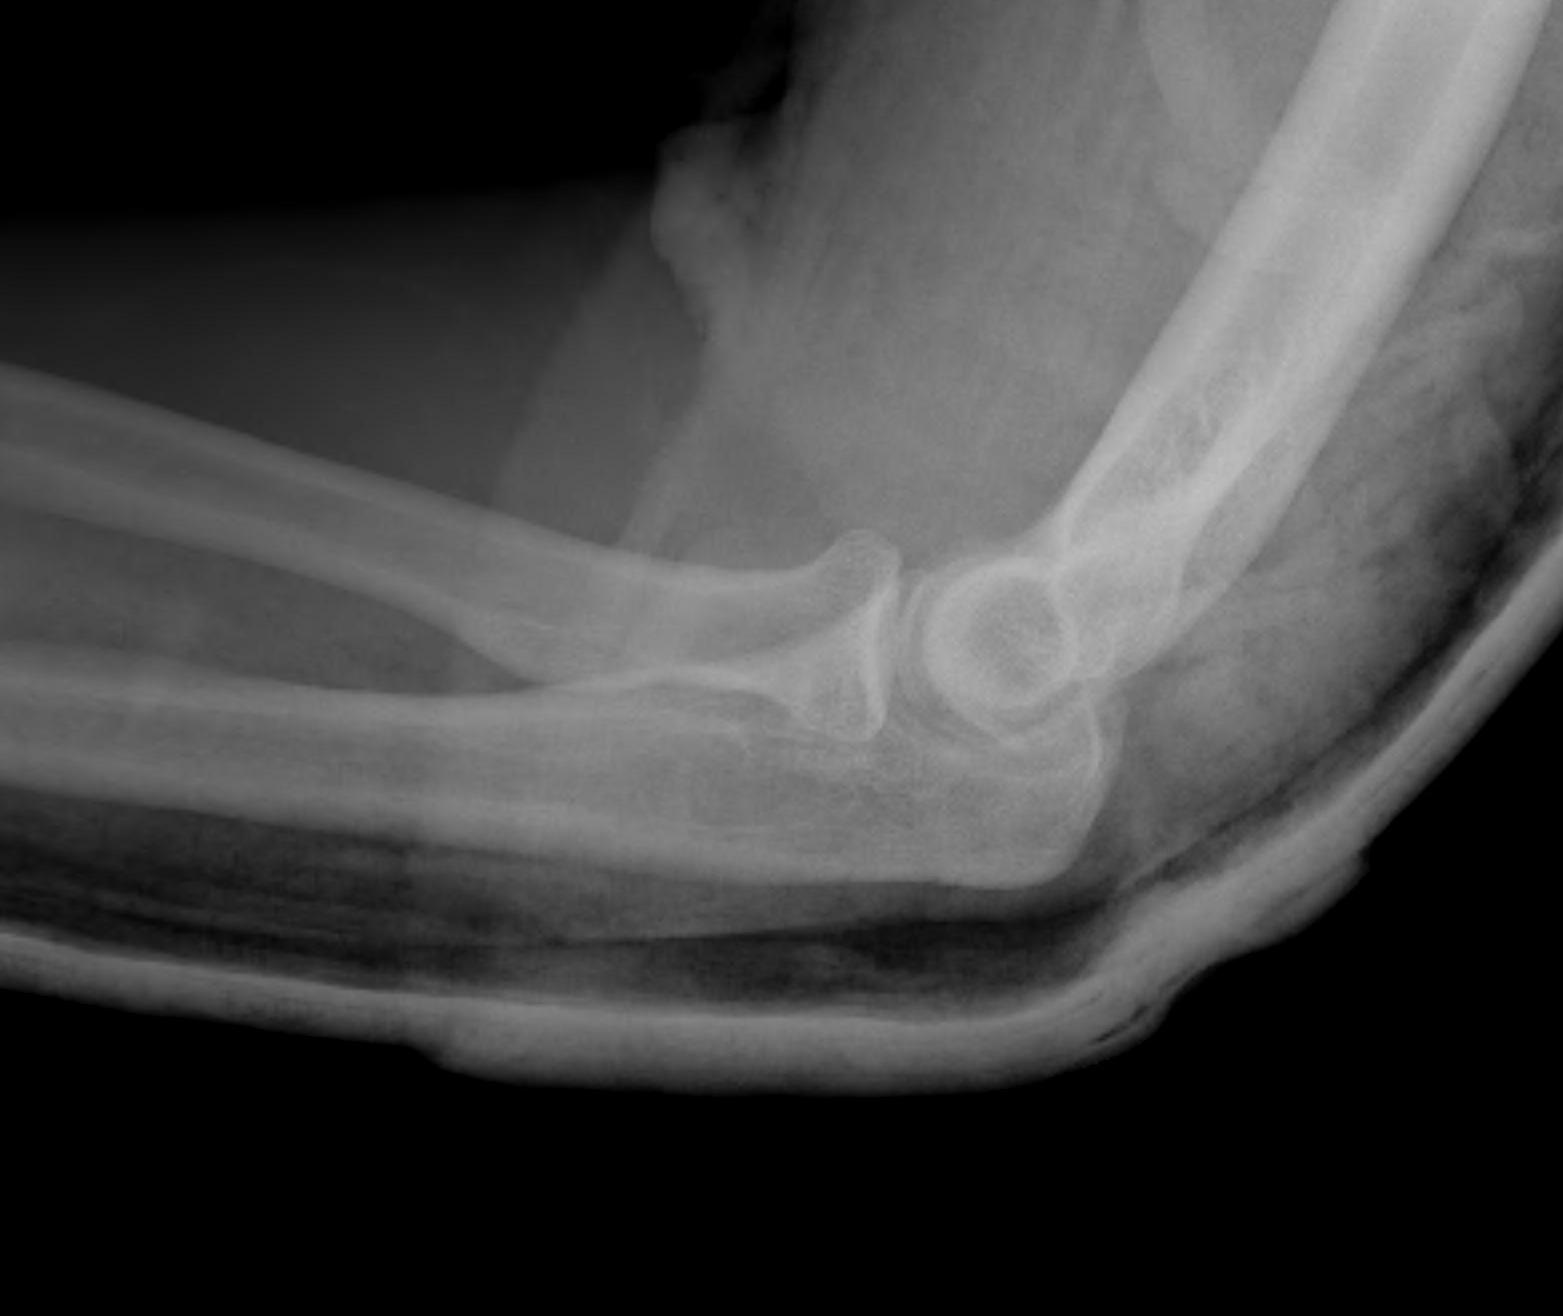

Posterolateral rotatory subluxation / instability

Incomplete posterolateral dislocation Coranoid perches on trochlea |

Stage 3A - posterior band MCL torn - anterior band MCL intact - posterior dislocation

After reduction elbow stable with hand pronated